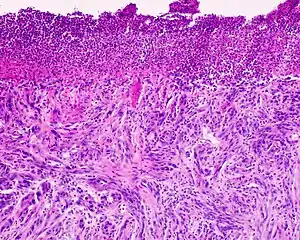

Desmoplastic melanoma is a rare cutaneous condition characterized by a deeply infiltrating type of melanoma[2]: 696 with an abundance of fibrous matrix.[3] It usually occurs in the head and neck region of older people with sun-damaged skin.[3] Diagnosis can be difficult as it has a similar appearance to sclerosing melanocytic nevi as well as some nonmelanocytic skin lesions such as scars, fibromas, or cysts.[3]